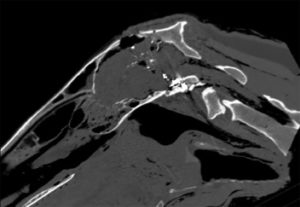

Infographic: How Does a CT Scan Work on Horses?

Computed tomography creates cross-sectional, 3D images to help veterinarians diagnose a variety of equine injuries and lamenesses.